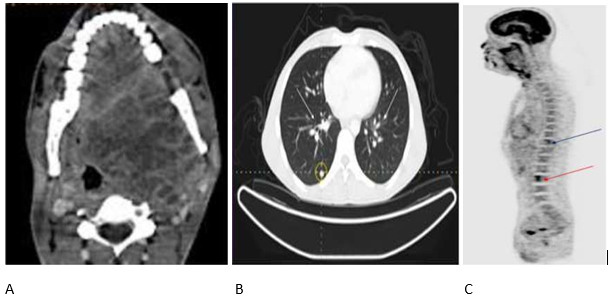

Case Presentation: A 38-year-old male presented with a metastatic carcinoma ex pleomorphic adenoma of the pharynx, with invasion into the carotid space. Diagnosis was confirmed histopathologically. The patient underwent palliative radiotherapy.